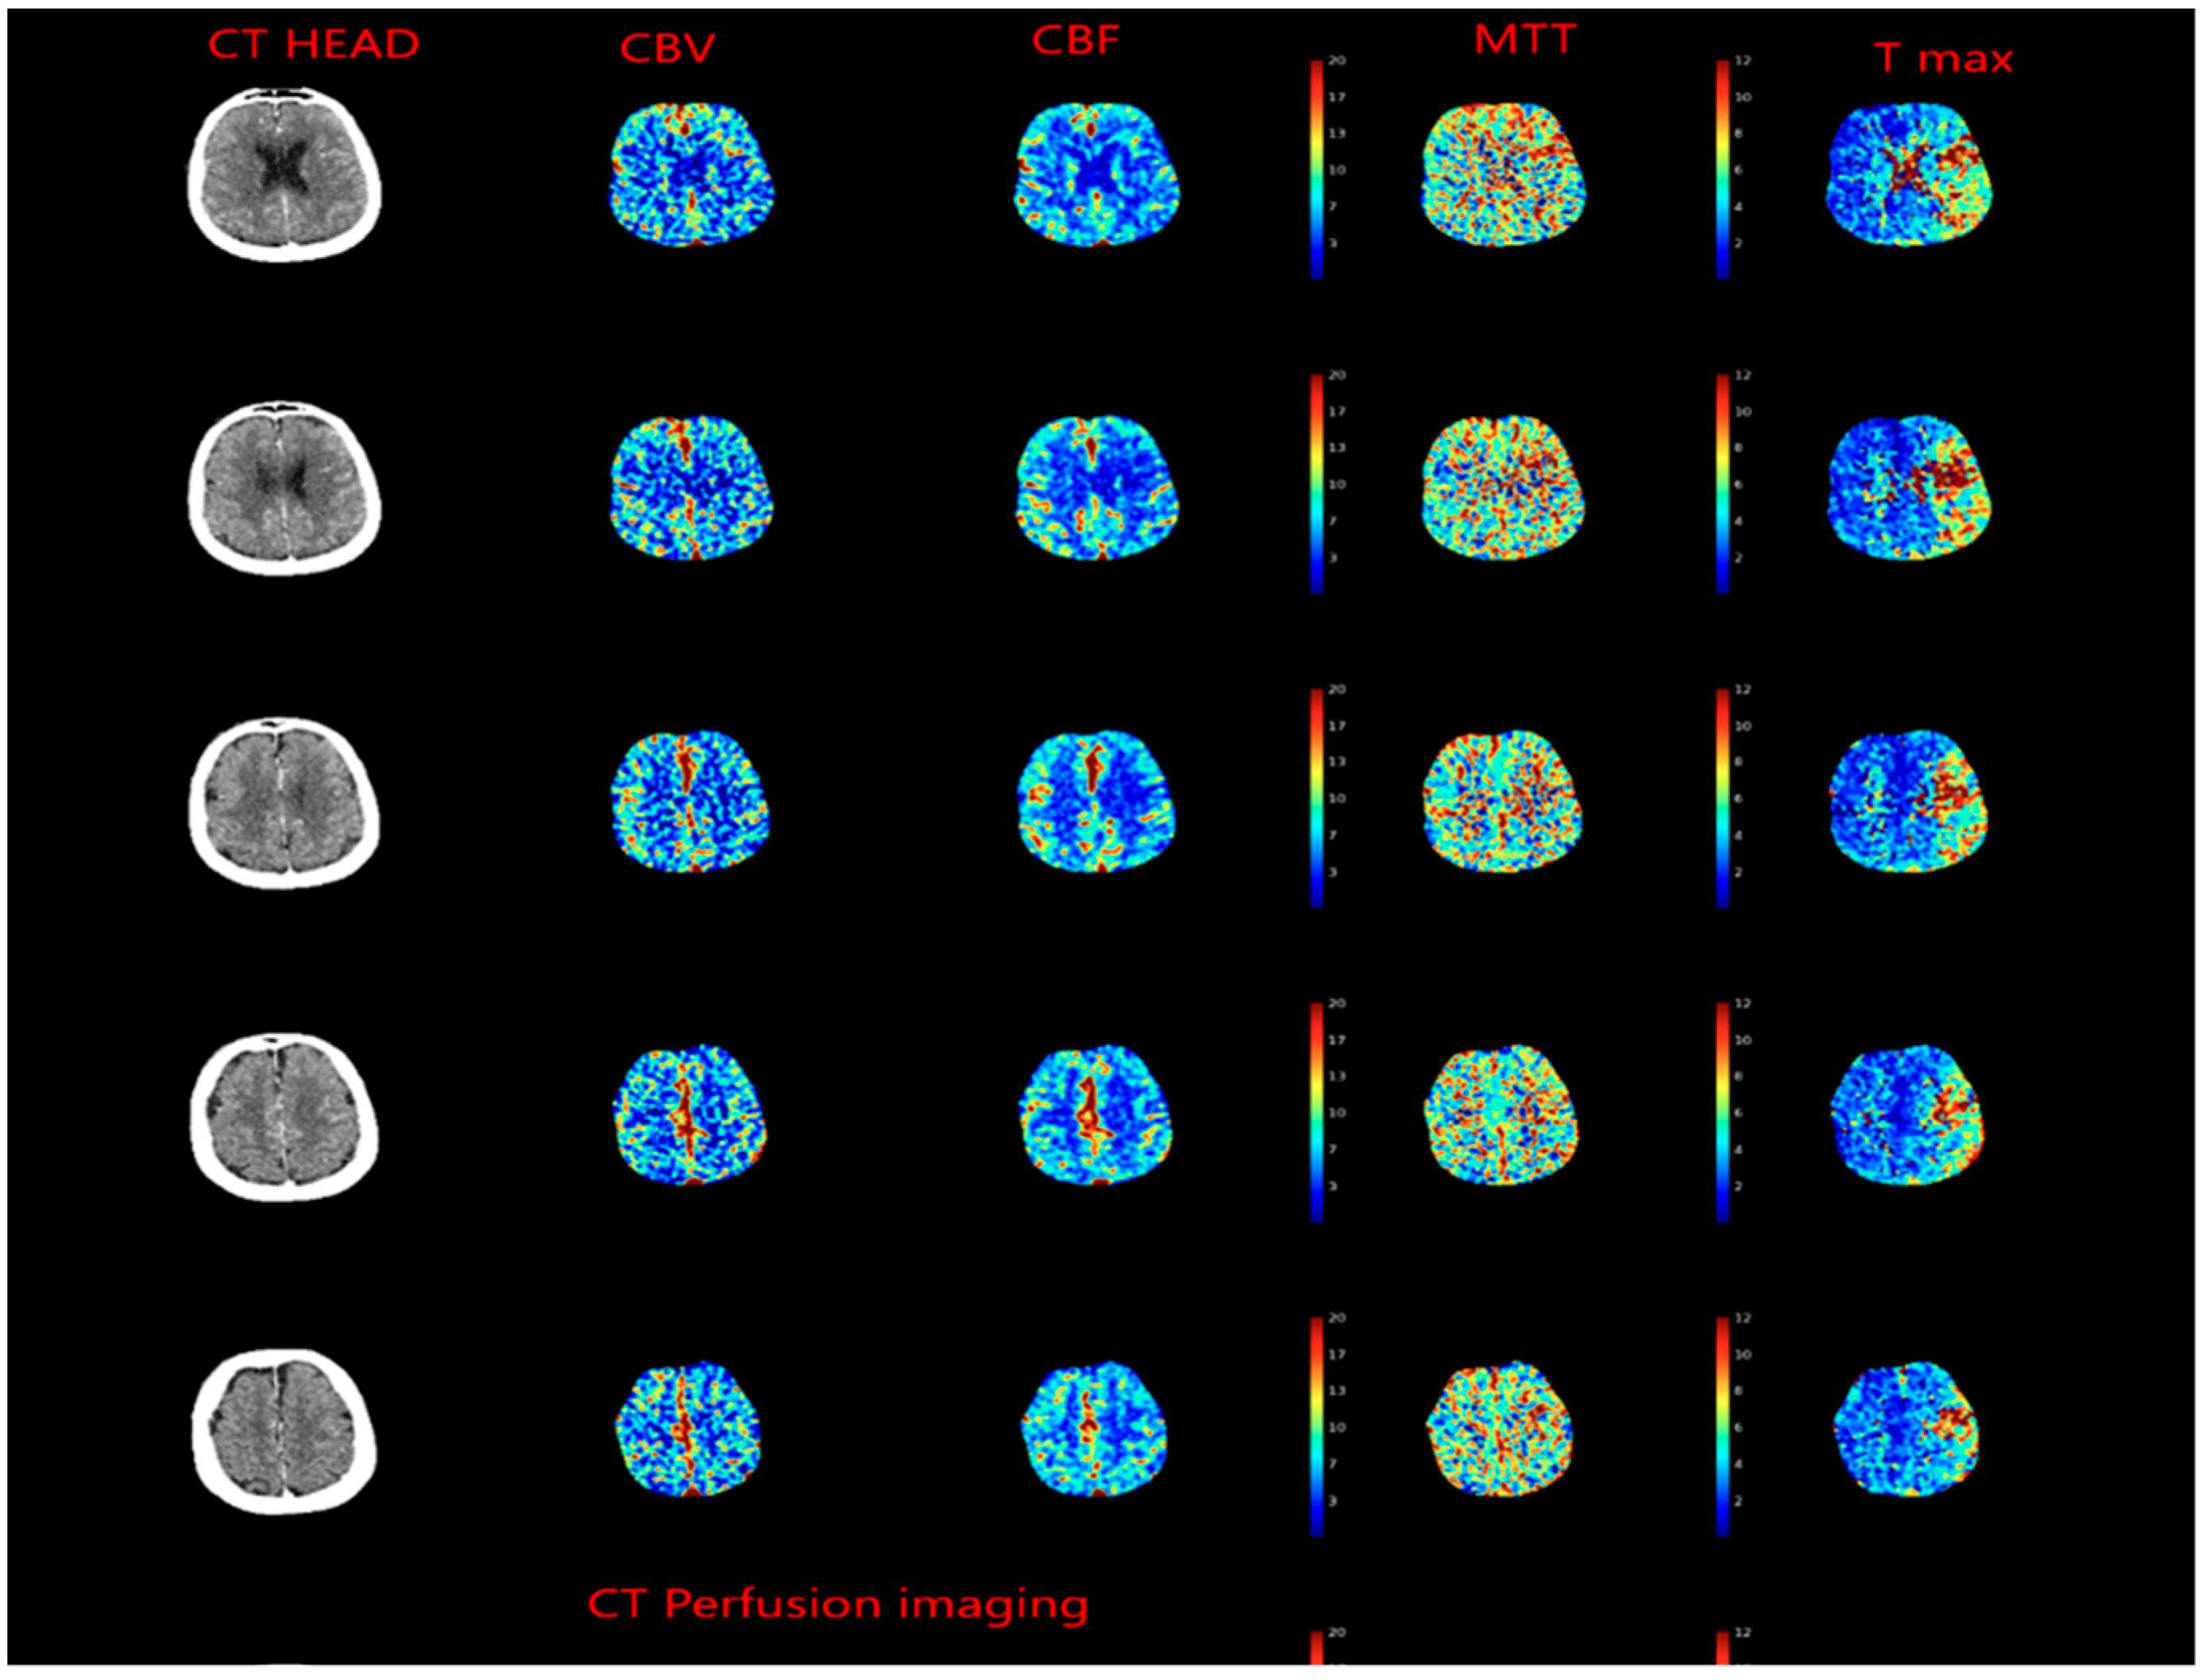

2.5. Evolution of the Concept of the Tissue Window and Late Window Trials